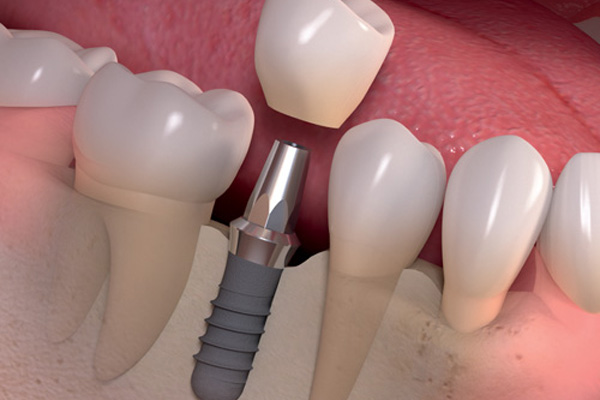

معلومات طبية